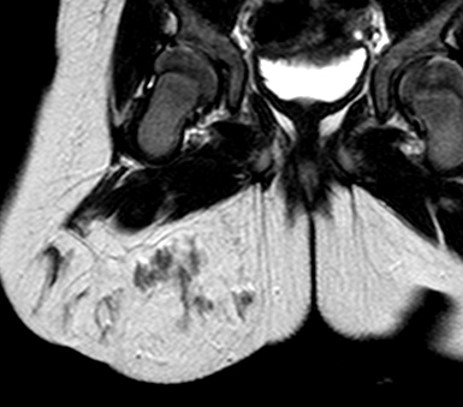

- 【参考症例】

男児

生下時からの右膝腫大

5歳:腫瘤周囲脂肪の増生と大腿四頭筋の萎縮・脂肪変性点状石灰化

15歳:大腿四頭筋腱や膝蓋腱に沿って広がる境界明瞭な腫瘤